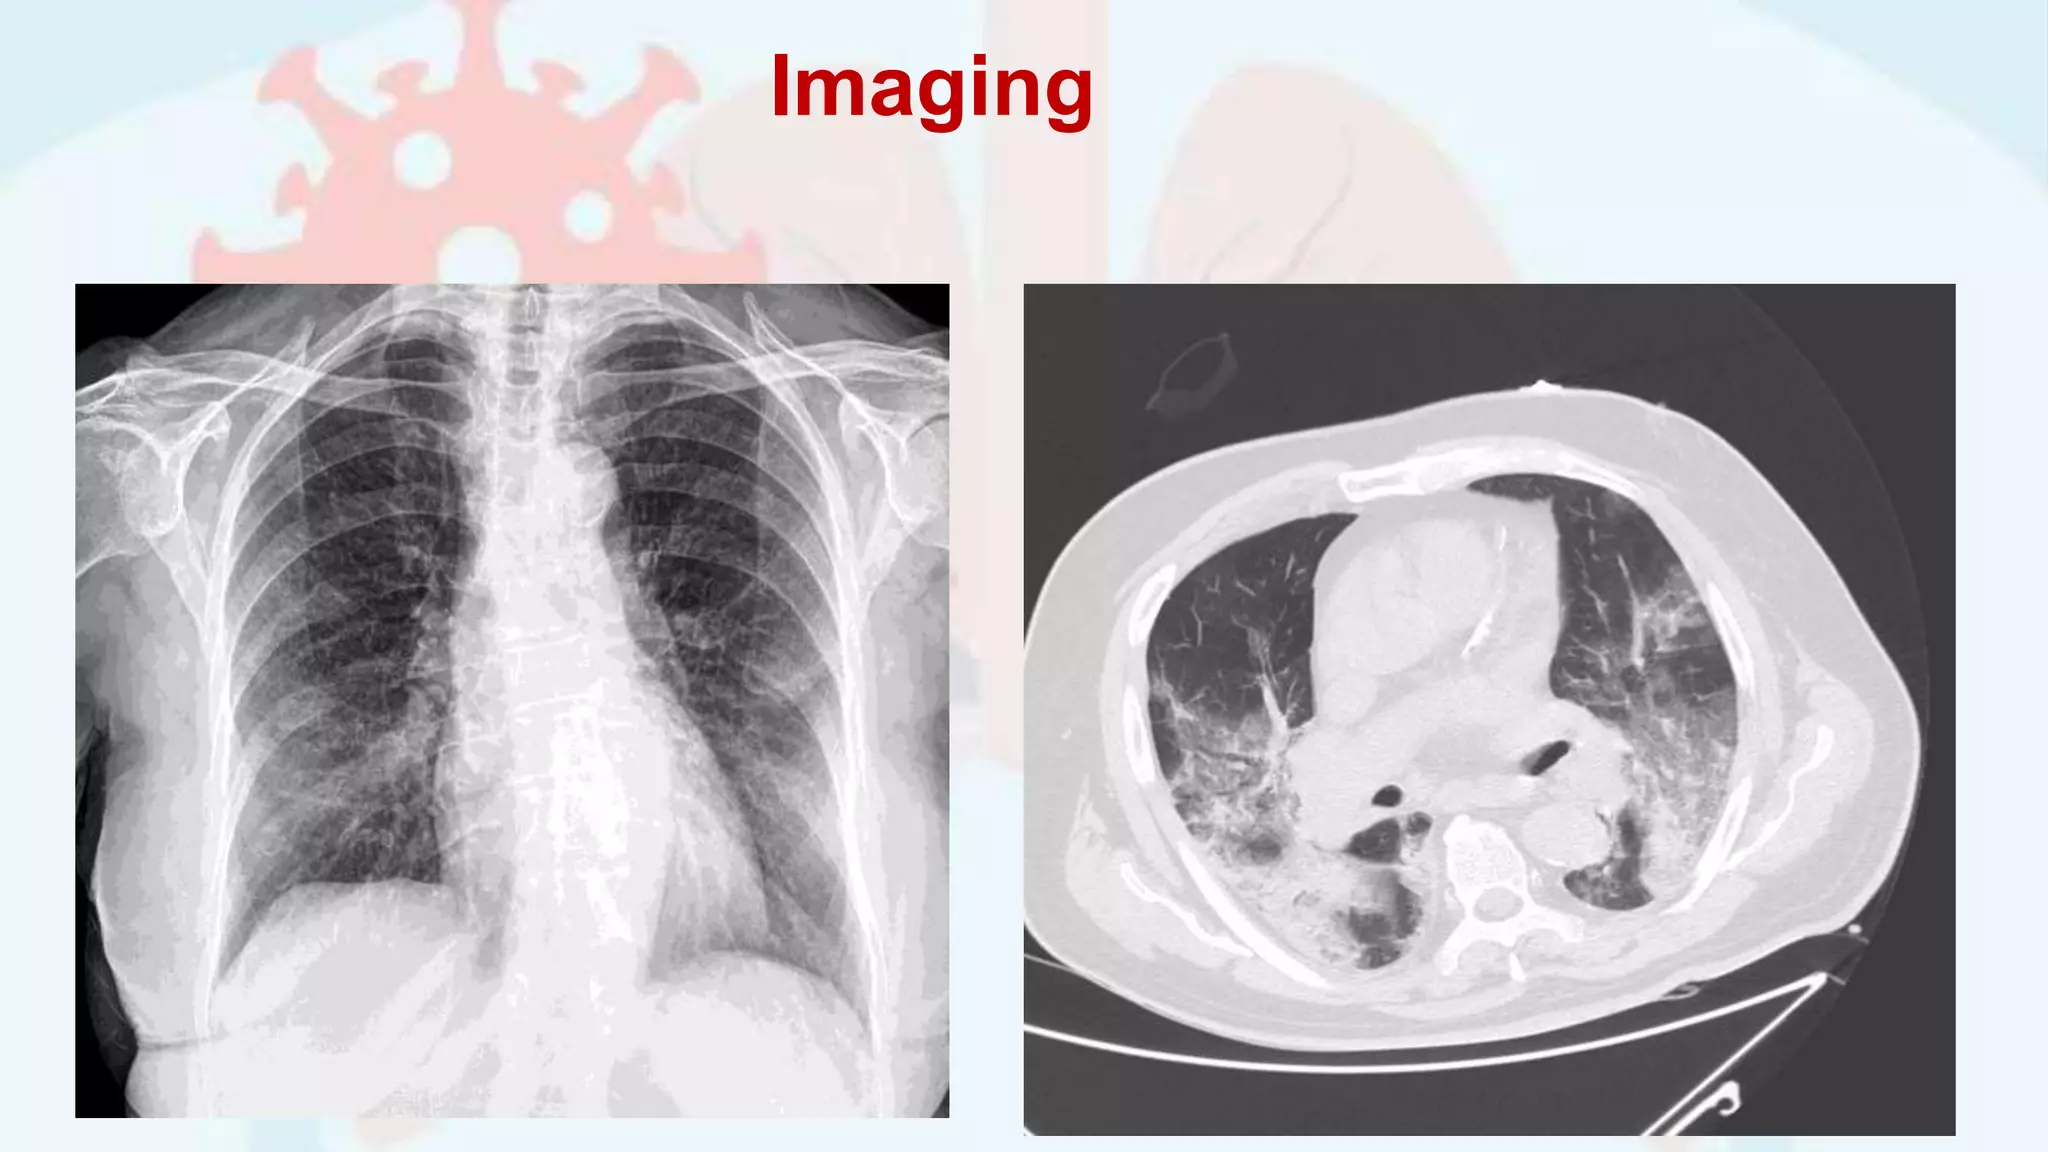

Imaging

• #6 Chest radiography remains the primary imaging modality like any other chest conditions. However, approximately two-third of Covid19 patients will have normal chest radiograph. Computed Tomography (CT) scans can be considered as a primary imaging modality for suspected Covid 19 patients as it has higher sensitivity for detecting the typical features of Covid19 pneumonia e.g. bilateral predominant ground-glass opacities with or without consolidation in the peripheral lung fields.